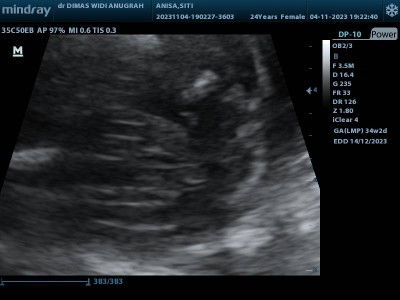

Usg anak kedua

Dok mau tanya apa bnr kalo JK garisnya ada 3 itu anak perempuan

mungkin ya bun. aku waktu hamil anak ke 2, usg di 32w jk perempuan jelas sekali bentuknya bergaris. sekarang hamil anak ke 3, usg 22w bentuknya seperti menonjol katanya sih jk laki2. bunda emang pas usg ga di jelasin sama dokternya?